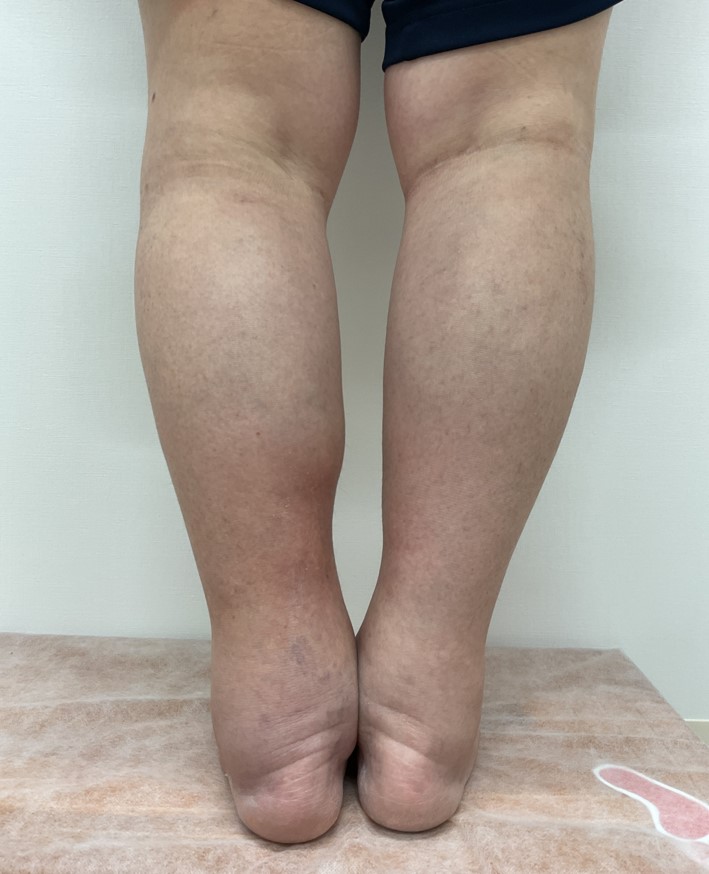

術前

術後